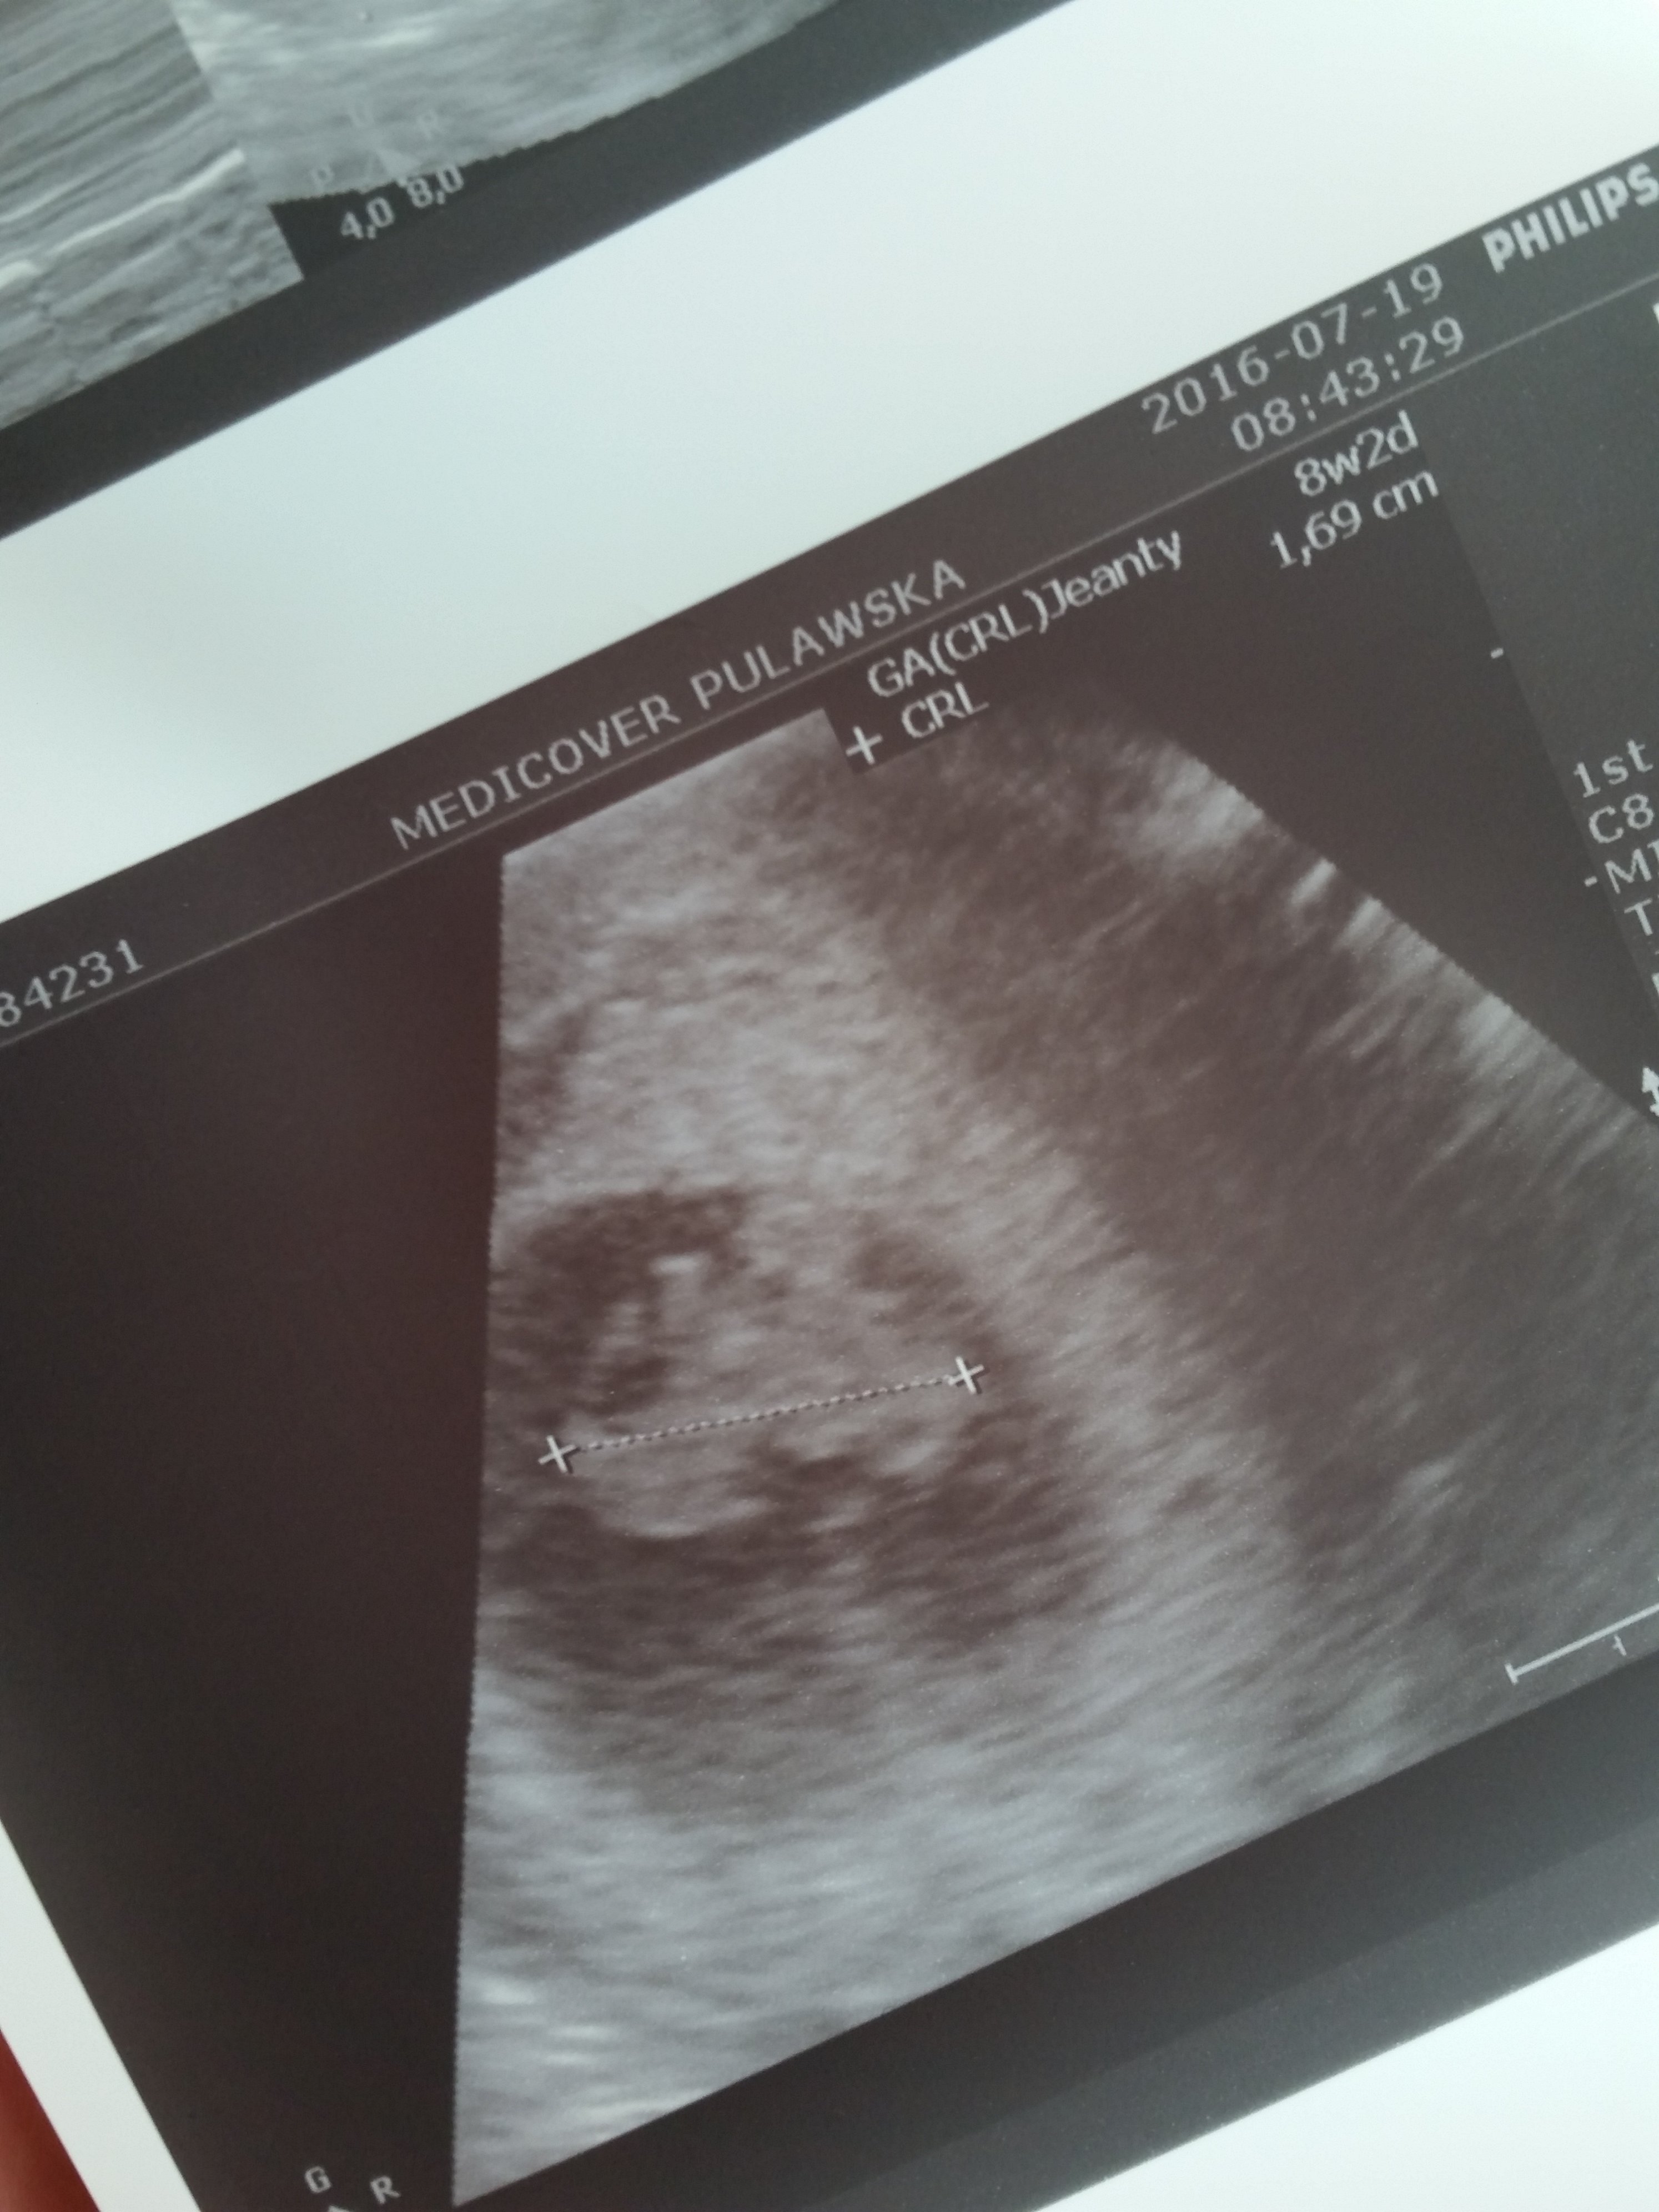

Super, gratulacjeJa dzisiaj byłam na usg prywatnie, bo za tydzień mam wizytę u gin i myślę, że warto mieć usg ze sobą.

Oto kropuś 6.5 mm z bijącym serduszkiem 121 u/min. [emoji173][emoji173][emoji173]Zobacz załącznik 763565

Ja dzisiaj byłam na usg prywatnie, bo za tydzień mam wizytę u gin i myślę, że warto mieć usg ze sobą.

Dokładnie! [emoji9][emoji9][emoji9]Gratulacje!!!! Piękne serduszko!!!!trochę kciuków trzymałyśmy za to serduszko więc serio super!!!